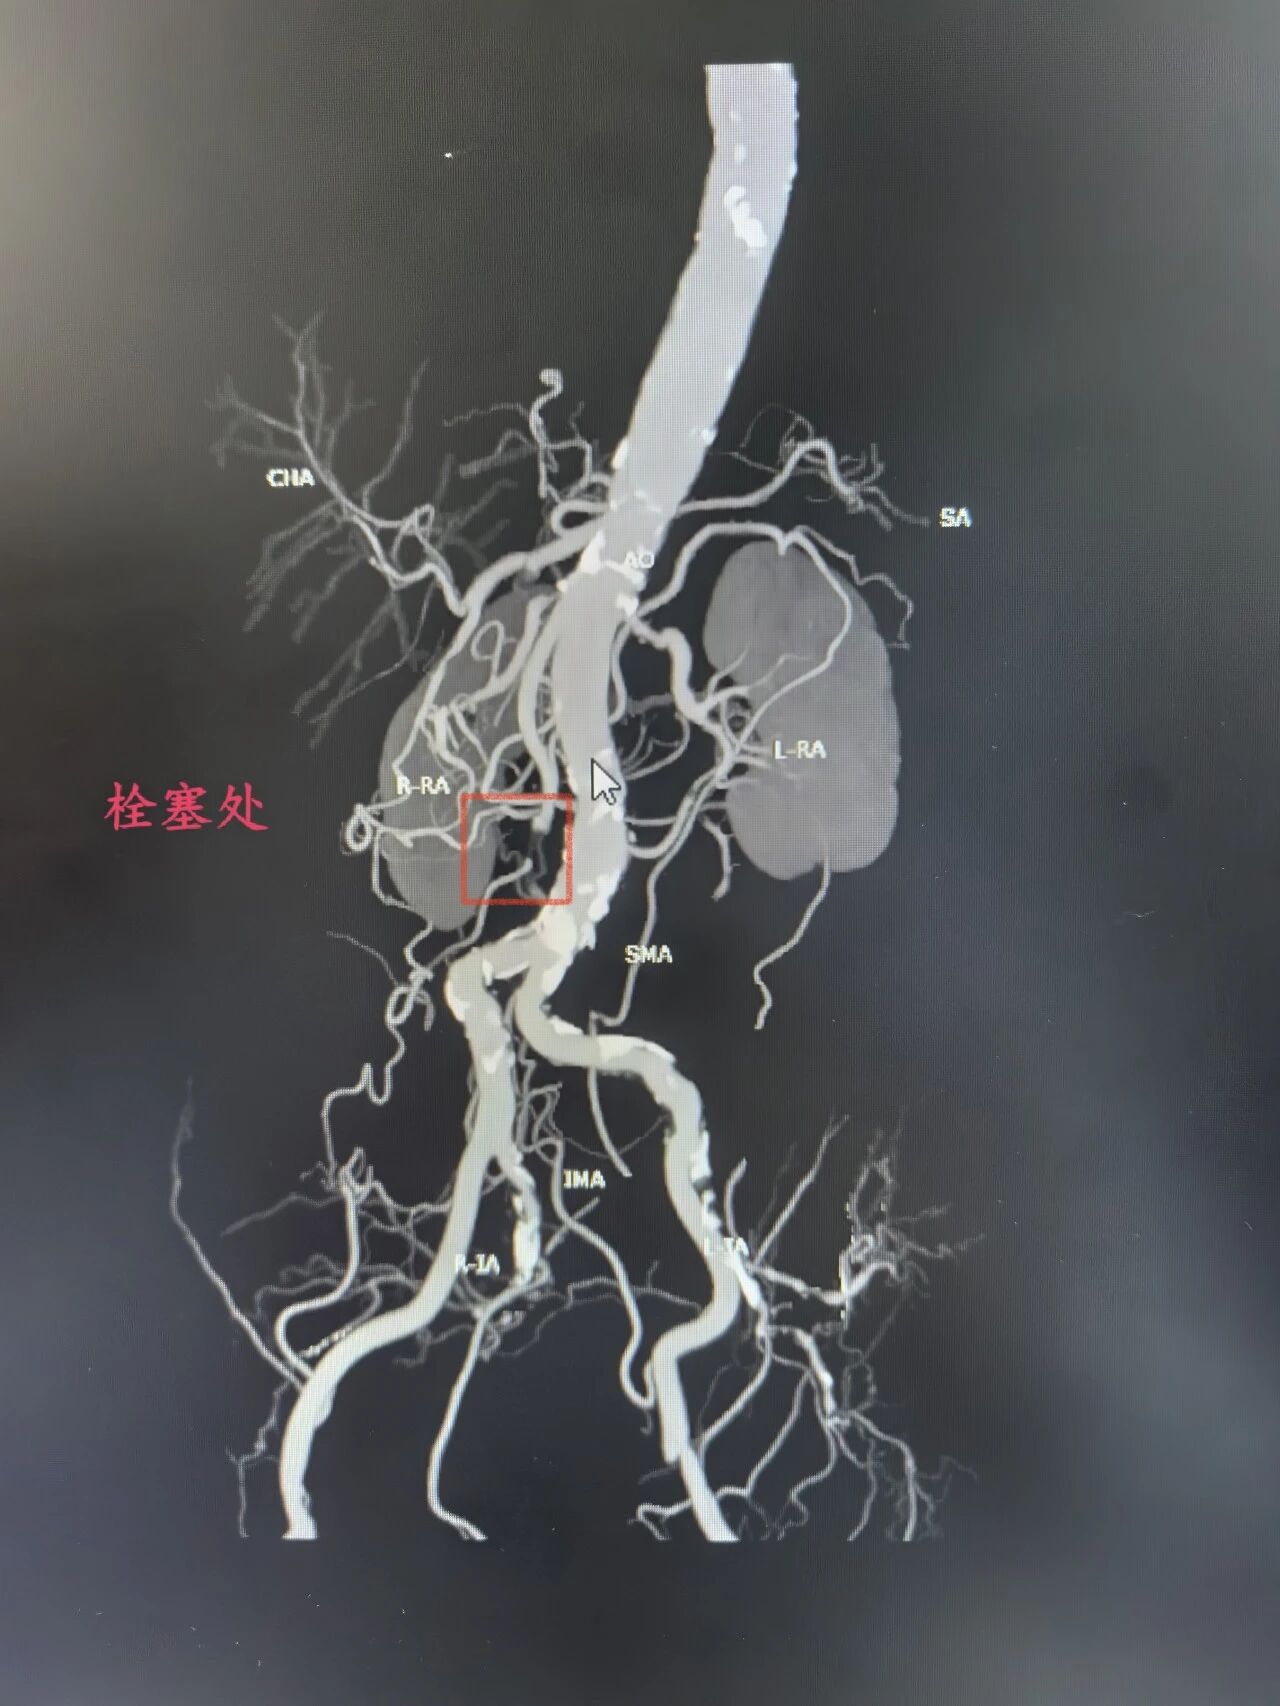

(资料图片)患者刘女士(化名)突发腹痛4.5小时,伴恶心呕吐、解稀便,紧急就诊于医院急诊科。刘女士有24年高血压、2型糖尿病病史,合并冠心病、心房颤动等多种基础疾病,还自行停用房颤抗凝药,身体基础条件差。急诊科接诊后迅速请血管外科会诊,冯涛副主任医师结合患者病史及症状,高度怀疑血管栓塞,建议完善肠系膜上动脉CTA检查。检查结果显示,患者肠系膜上动脉远段及胃左动脉、脾动脉近段动脉栓塞并脾梗死,同时合并腹主动脉、髂动脉多发狭窄等,病情危急,随时可能因肠管缺血坏死危及生命。

时间就是生命,鉴于患者高龄、基础病多,因传统开腹手术创伤大、风险高,术后并发症多,恢复时间较长。血管外科团队反复评估病情,与家属充分沟通后,决定采用微创介入手术治疗。科室迅速启动急诊手术绿色通道。术中,发现患者肠系膜上动脉起始处、距起始12cm处重度狭窄,15cm处完全闭塞,双侧肾动脉也有不同程度狭窄。随后,血管外科团队采用外周斑块切除系统清除肠系膜远端血栓,对重度狭窄处球囊扩张,操作精准、高效。术后造影显示,患者肠系膜上动脉管腔明显改善,血流量显著增加,无造影剂渗漏,手术成功,患者安返病房。